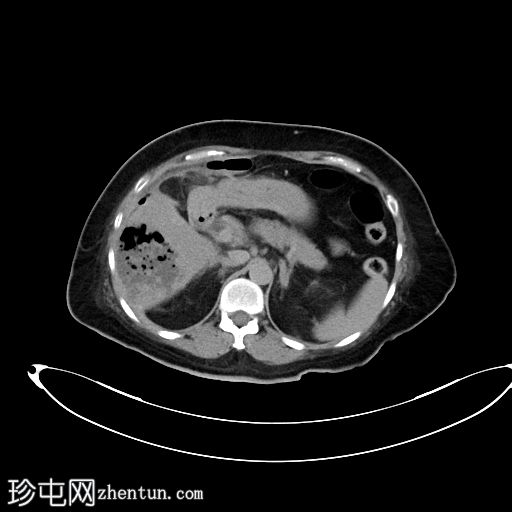

CT

轴位

非增强

4.jpg

肝段 6 和 7 可见多房性积液,呈环状强化

积液内可见多个气体腔

破入肝包膜下间隙,可见肝包膜下积液及气体腔

壁层腹膜与前腹壁之间可见另一局灶性积液

肝段 7 的肝内胆管局灶性扩张(0.3cm),内含气体腔

其他肝内胆管和肝外胆管均正常

胆囊缺失,可能由于既往胆囊切除术所致

无游离液体。

双侧肾皮质囊肿

轻度右侧胸腔积液伴邻近肺不张